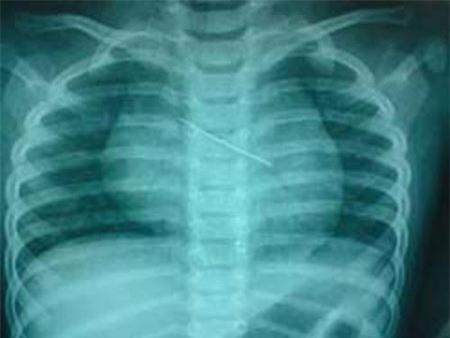

Hình ảnh X-quang ngực có kim băng

Bệnh nhân là Lê Anh Th., ở Xuân Lộc (Hà Tĩnh). Theo lời kể của người nhà bệnh nhân, trong lúc ngồi chơi cùng bà và mẹ, cháu Th. nhặt được chiếc kim băng của bà làm rơi và cho vào miệng. Mẹ cháu hốt hoảng dùng tay móc miệng cháu để lấy kim băng ra. Cháu khóc thét và nuốt vật này vào sâu hơn. Lập tức gia đình đưa cháu đến BV tỉnh Hà Tĩnh, kết quả chụp X-quang phát hiện kim băng đã nằm trong lồng ngực của trẻ.

Tại BV Nhi Trung ương, kết quả chụp X-quang ngực thẳng và nghiêng cũng cho thấy có hình ảnh kim băng nằm trong đường thở, tận phế quản góc trái. Đặc biệt, kim băng ở trạng thái mở, đầu nhọn quay lên trên và ngập sâu vào niêm mạc phế quản. Sau khi hội chẩn, các bác sĩ đã quyết định mổ nội soi phế quản để lấy dị vật. Ca phẫu thuật diễn ra trong 2 giờ đồng hồ. Bệnh nhi sau đó đã bình phục, sức khỏe tốt và được xuất viện.